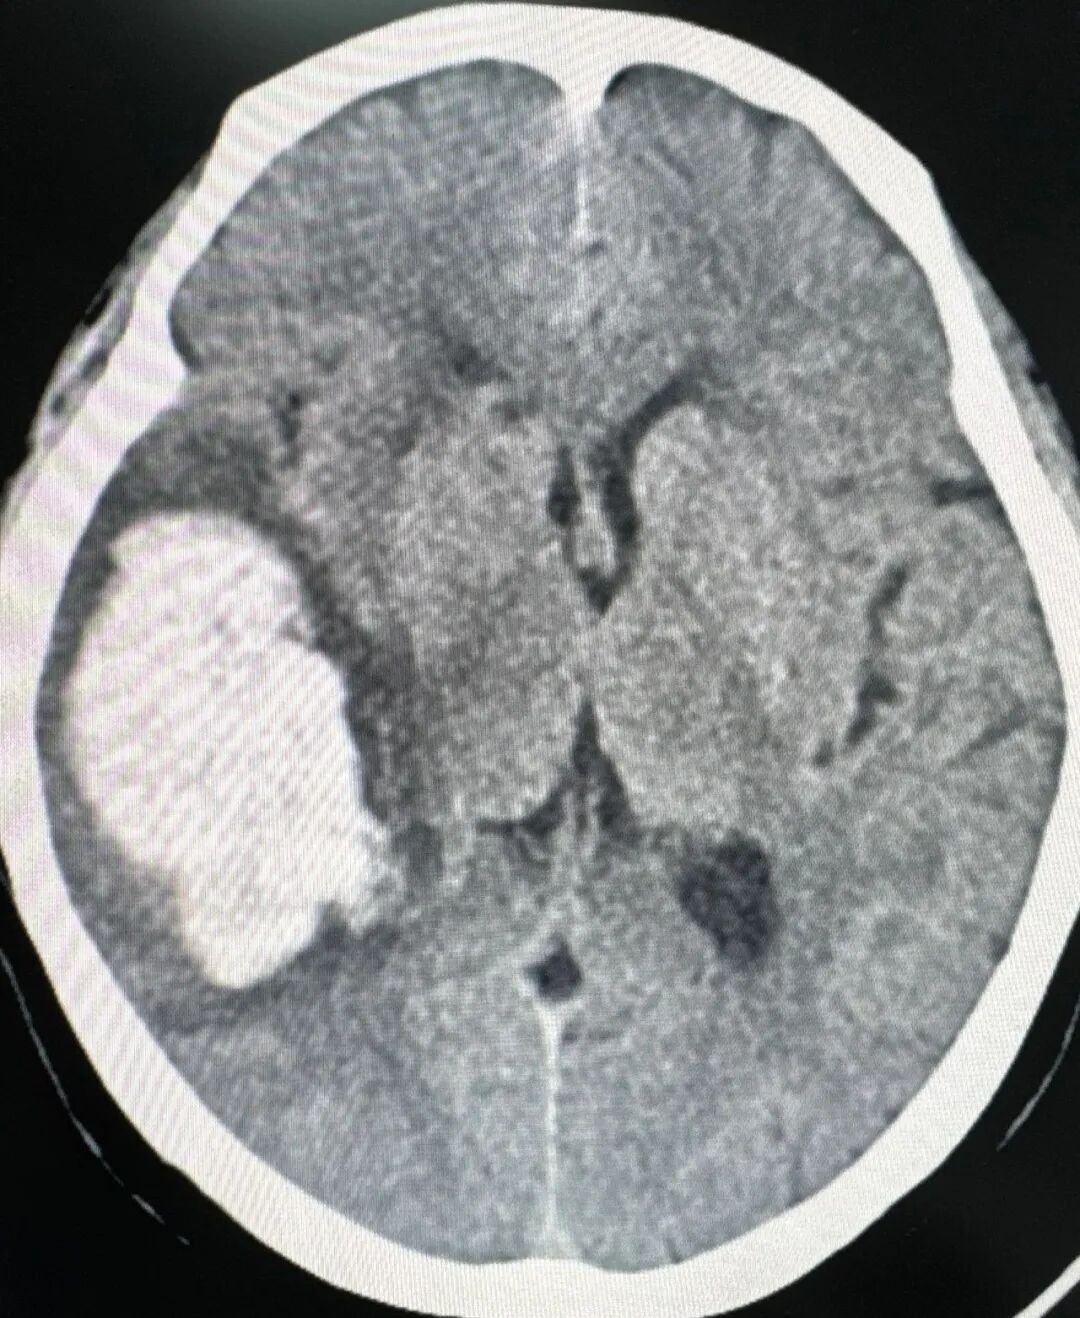

头颅CT检查提示:右侧颞顶叶脑出血

接受手术的是一名73岁脑出血患者。该患者突发头痛持续长达5小时,被家人急送至陕西冶金医院。经头颅CT检查结果提示:右侧颞顶叶脑出血、出血量40ml。